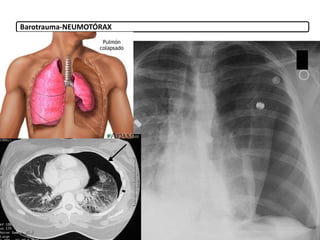

o Barotrauma: Por aumento de la presión en el pulmón (0,5-

– Neumotórax

Barotrauma-NEUMOTÓRAX

9.3. Derivadas dela presión positiva 9. Complicaciones Ventilación mecánica o Barotrauma: Por aumento de la presión en el pulmón (0,5- 30%) (presiones >35- 40 cm H2O) – Neumotórax – Enfisema subcutáneo – Neumomediastino o Volutrauma: Por ventilar con un volumen excesivo. o Atelectrauma: Por abrir y cerrar continuamente sus alveolos. Hay que valorar PIF, pico de flujo inspiratorio, evitando el colapso en espiración. o Biotrauma: respuesta fisiológica al estrés mecánico inducido por la ventilación. o Infecciones: neumonía o Toxicidad por O2